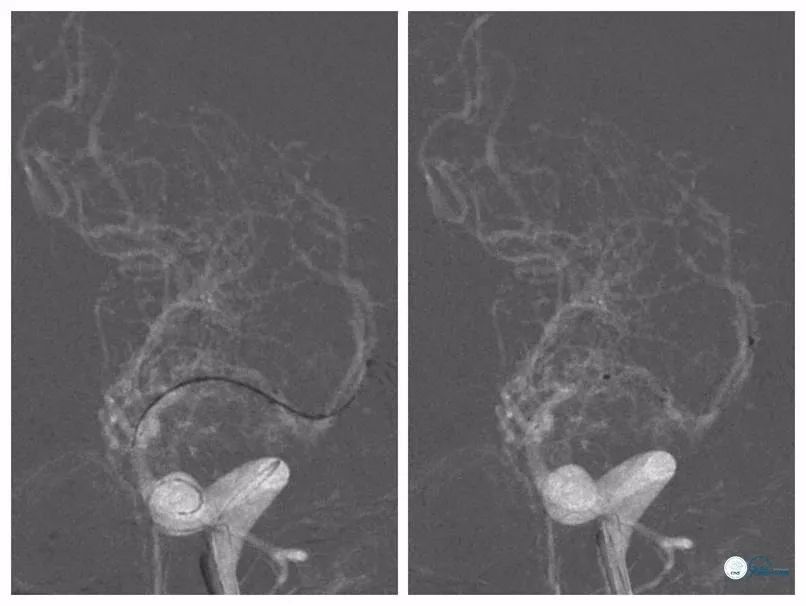

全麻下右股动脉入路,6F导引导管至左侧颈内动脉C2段,路径图下送入Pilot 50(0.014”,190cm)微导丝与Echelon-10微导管同轴通过狭窄段。微导管造影提示位于真腔内(图8)。

图8